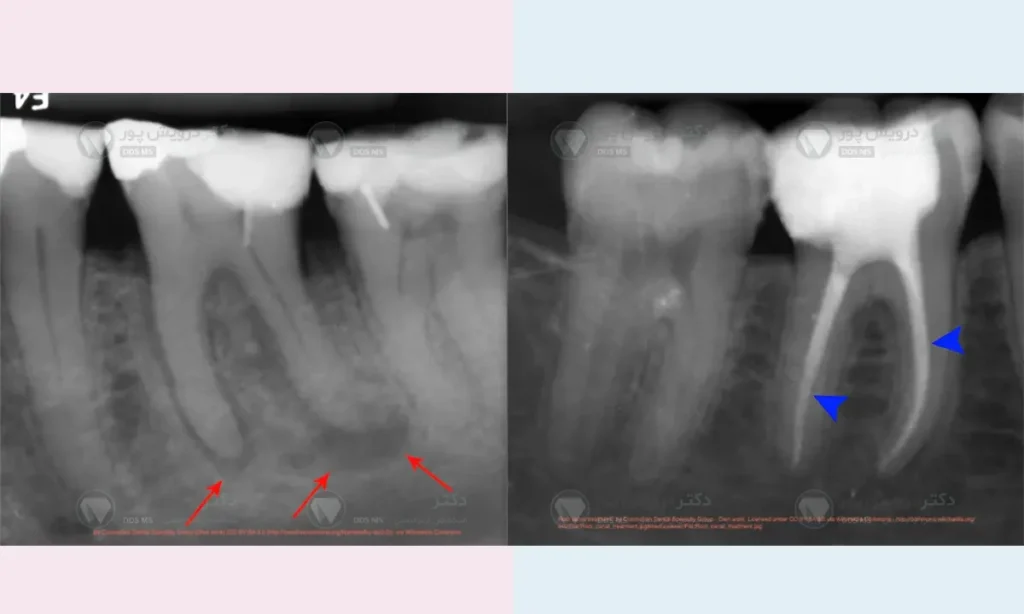

ممکن است قبل از شروع ارتودنسی، یک پوسیدگی کوچک و پنهان (به خصوص بین دندان ها) وجود داشته که در معاینات اولیه دیده نشده است. وجود دستگاه های ارتودنسی، رعایت بهداشت را سخت تر کرده و این پوسیدگی با سرعت بیشتری پیشرفت کرده و خود را به عصب دندان رسانده است.

تحریک ناشی از تراش های قبلی

اگر دندان شما قبلاً یک پرکردگی بسیار عمیق داشته، ممکن است عصب آن از قبل در آستانه التهاب بوده و نیروهای ارتودنسی این التهاب را تشدید کرده باشند.